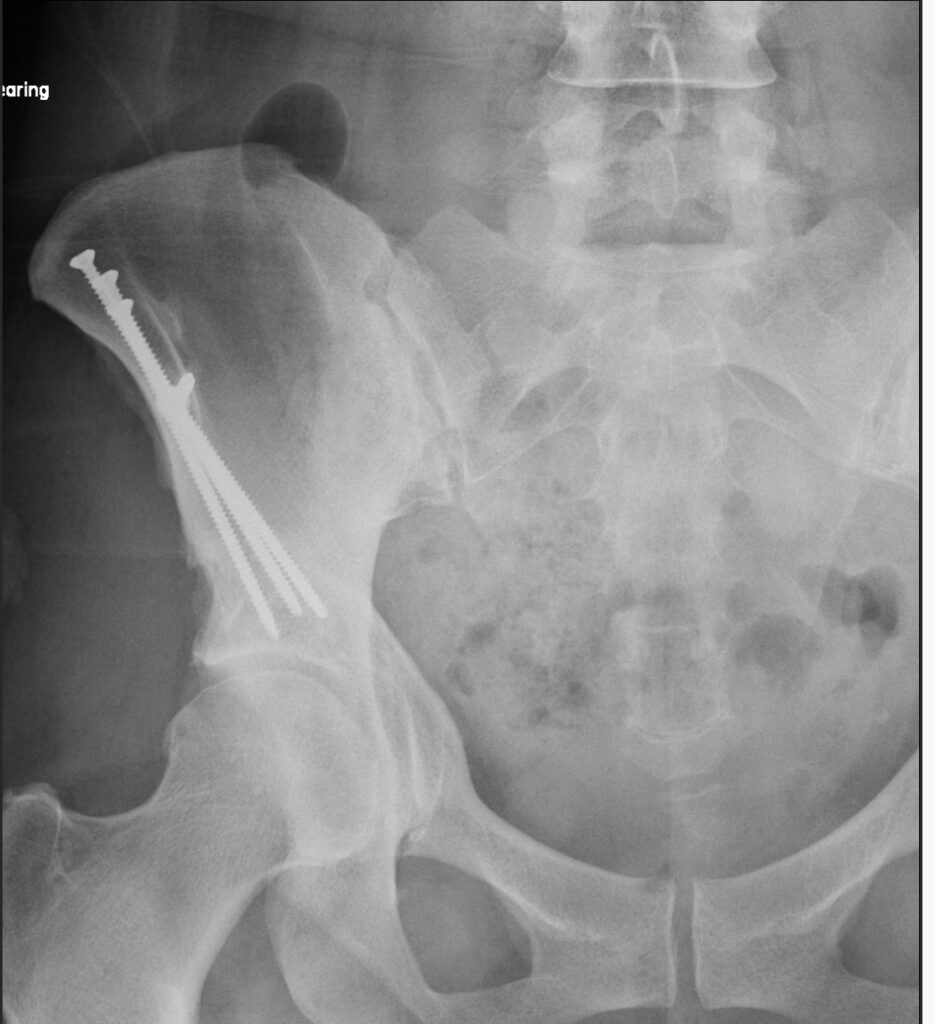

Periacetabular Osteotomy (aka PAO)

What is a PAO?

During the procedure the pelvis is cut in multiple places, the hip socket is repositioned and screws are used to secure it.

The goal is to improve coverage of the femoral head and preserve your natural hip joint.